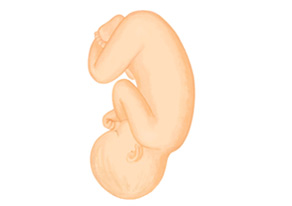

おなかの赤ちゃんの成長【32~35週ごろ】

●皮下脂肪が増え、体つきがふっくらして、外見的には新生児とほとんど同じようになってきます。

●35週になると肺の機能が成熟してきます。

●寝たり起きたりを20分おきに繰り返しています。

●髪の毛が長くなり、つめは指の先端まで伸びてきます。

肺の機能も成熟し、皮下脂肪がついてふっくらとしてきます。生後すぐのころの赤ちゃんの外見に近いでしょう。循環する羊水量が少しずつ減って、子宮内で赤ちゃんが動くスペースも狭くなります。